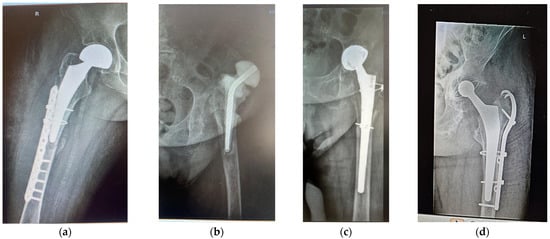

Bone–Ti-Alloy Interaction in Hip Arthroplasty of Patients with Diabetes, Dyslipidaemia, and Kidney Dysfunction: Three Case Reports and Brief Review

by Cosmin Constantin Baciu, Ana Maria Iordache, Teodoru Soare, Nicolae Catalin Zoita, Cristiana Eugenia Ana Grigorescu and Mircea Bogdan Maciuceanu Zarnescu

Medicina 2025, 61(12), 2228; https://doi.org/10.3390/medicina61122228 - 17 Dec 2025

Background and Objectives: Organ dysfunctions affect the quality of bone and body fluids. This case report seeks links between the underlying conditions of three patients undergoing hip arthroplasty (HA) with uncemented implants, the quality of their bones, and their Ti-6Al-4V orthopaedic implants, [...] Read more.

Background and Objectives: Organ dysfunctions affect the quality of bone and body fluids. This case report seeks links between the underlying conditions of three patients undergoing hip arthroplasty (HA) with uncemented implants, the quality of their bones, and their Ti-6Al-4V orthopaedic implants, on different time spans. Femoral stems are investigated. A brief review supports our findings. Materials and Methods: Cases: two women (F1 35+, F2 80+), and one man (M 65+), all having diabetes, dyslipidaemia, and kidney dysfunction. Samples: a segment of a broken 7-year-old stem, bone with a metallic layer, soft tissue, segments of one spare stem, and synthetic plasma enriched with glucose and urea according to the biochemistry tests of the respective patients. Vast studies show that cholesterol influences bone quality only. The stem pieces were ultrasonicated for 7 h at 37 °C in synthetic plasma. Scanning electron microscopy (SEM), energy dispersive X-ray spectroscopy (EDX), and profilometry investigated the Ti-alloy samples, electrochemistry analysed the post-sonication plasma, and histopathology examination was performed on the soft tissue remnants on the broken stem. Results: EDX show that all stem samples are Ti-6Al-4V with minute additions of other elements and hydroxyapatite (HAp) coating. SEM and profilometry analysis are consistent for the roughness in the outer layers of the stems. Electrochemistry on the bone fragment shows migration of vanadium during the 6 months since fracture to revision for M. Conclusions: Stems in altered synthetic plasma are affected by glucose and urea. Metal migration from the prostheses can occur through the chemical interactions between body fluids with abnormal biochemistry and the orthopaedic prostheses, favoured by cracks and concurring with wear following friction during usual movements. Cholesterol influences on the bone quality. Full article